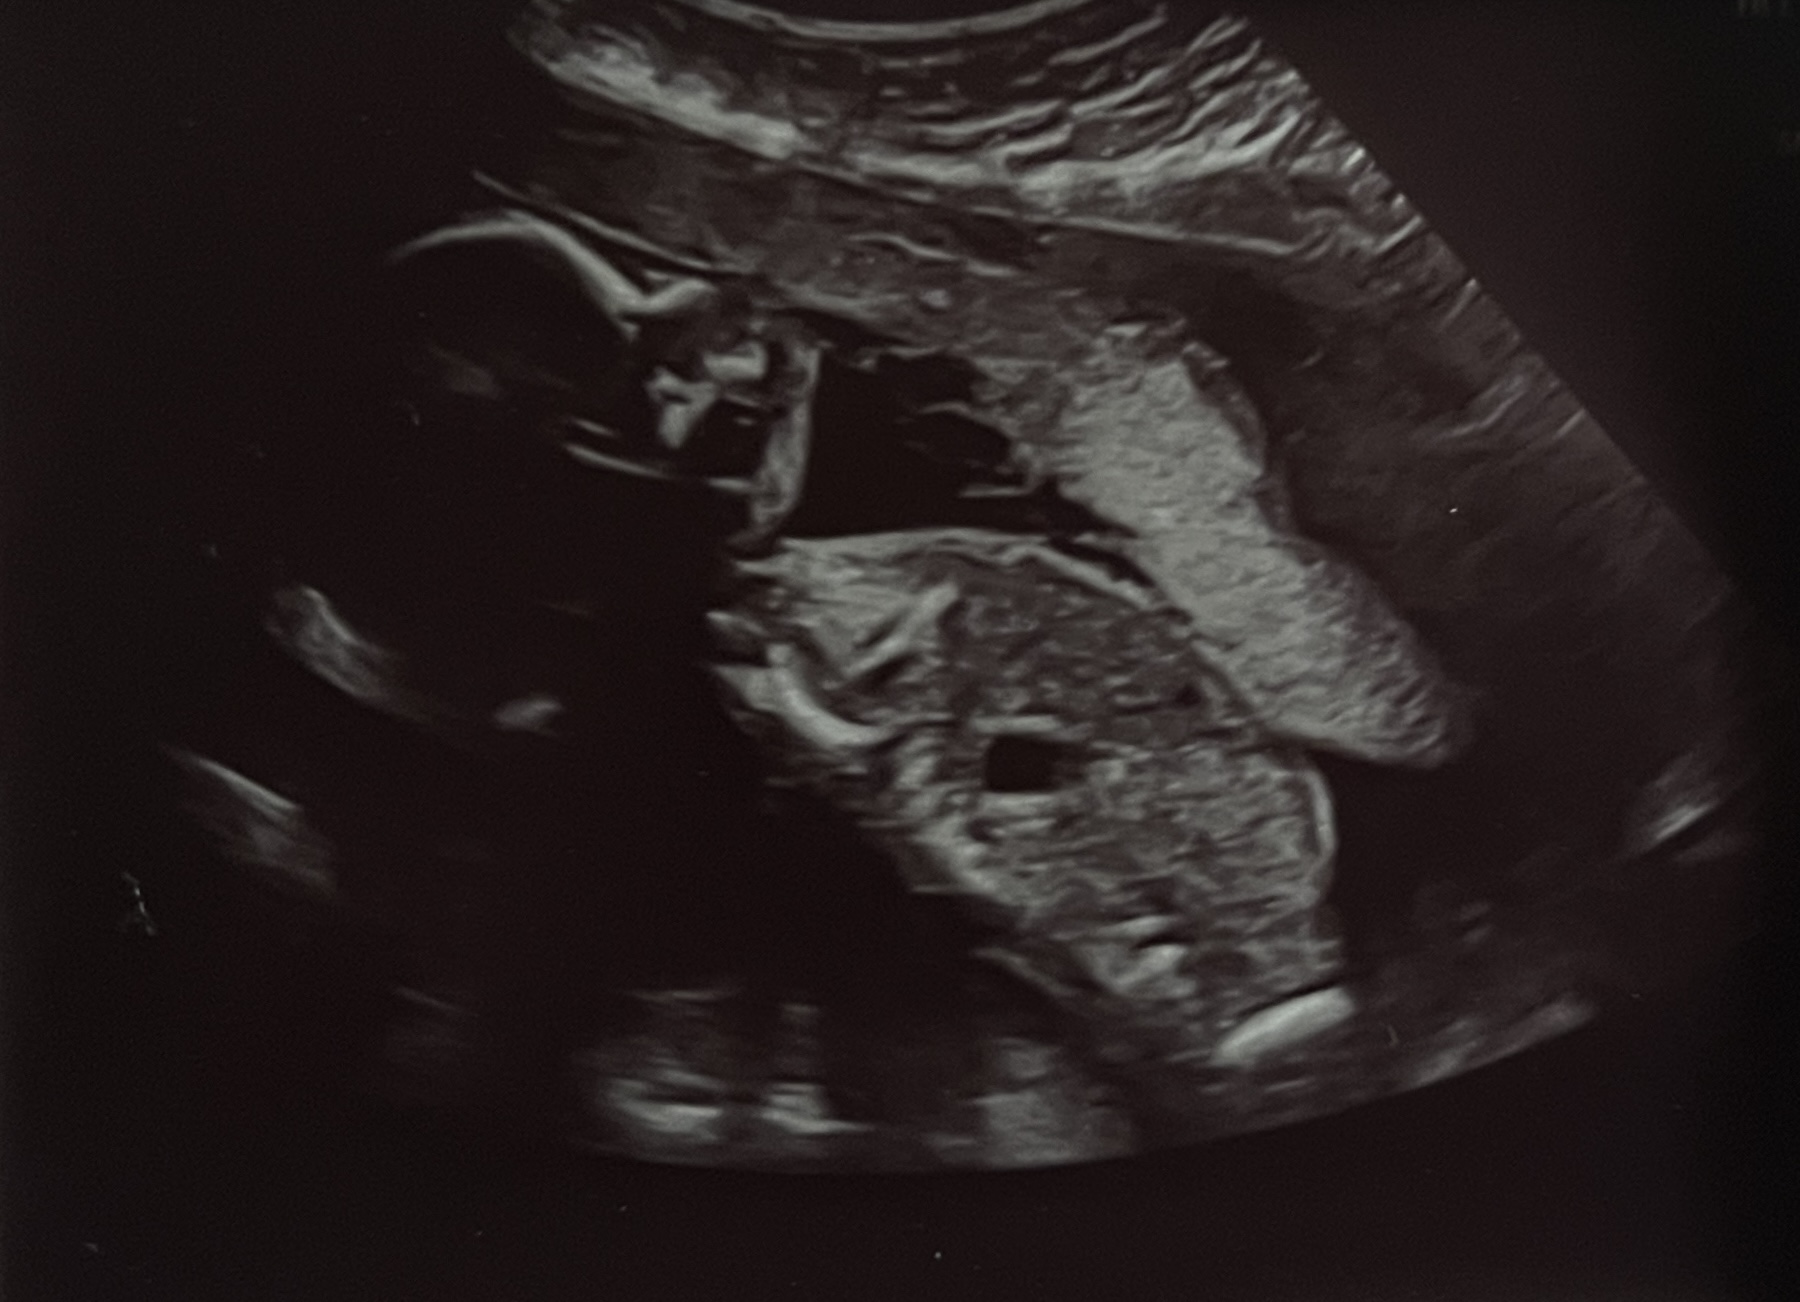

Baby Ultrasound

Loading...